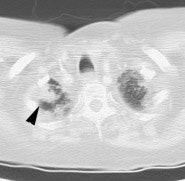

Metastatic head and neck cancer with secondary lung malignancy: The patient shown below had a history of head and neck cancer. The PET scan demonstrated a metastatic lesion to the right temporal bone. Also noted was intense uptake in the right lung apex(black arrow below right)- on CT this was felt to represent scarring (black arrowhead). FDG uptake is highly suggestive of a separate primary lung cancer. |